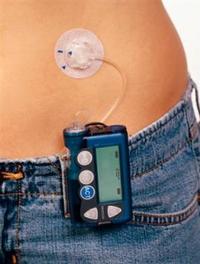

La prise en charge de l’adolescent diabétique représente un défi pour l’obtention d’un contrôle glycémique en raison des modifications [...]

Selon l’OMS, le diabète affecterait actuellement 8,5 % de la population mondiale et sa prévalence ne cesse d’augmenter. Malgré les [...]